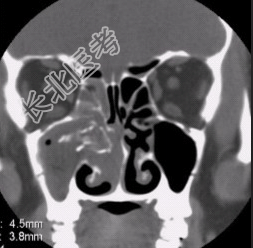

- [材料题] 患者男,35岁,鼻腔分泌物多,流脓涕,鼻塞,头痛,面部局部压痛1个月余。体检:鼻腔分泌物多,鼻黏膜肿胀。CT表现如下图。

- 简答题1、请问该患者最可能的诊断是什么?

- 简答题2、请问慢性化脓性鼻窦炎影像学表现有哪些?